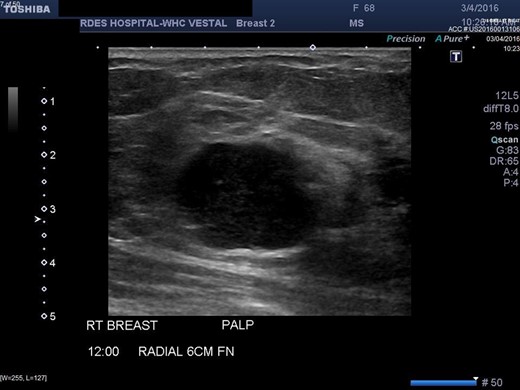

A diagnostic mammogram and ultrasound were performed to evaluate the right breast mass. The right breast imaging was categorized as BIRADS 5 (Figs 1–3). The patient underwent a right breast ultrasound-guided vacuum core biopsy of the mass and a fine needle aspiration (FNA) of the enlarged lymph node in the right axilla. Pathology of the core biopsy revealed poorly differentiated squamous cell carcinoma with tumor necrosis and calcification (Figs 4 and 5). Cytology of the right axillary lymph node was negative for metastatic carcinoma.

Right breast ultrasound demonstrates an irregular shaped, hypoechoic solid mass, located adjacent to the pectoralis muscle. This corresponds to the abnormal mammographic density noted in Figures1 and 2 and to the palpable abnormal finding on the clinical breast exam.

There are no specific mammogram or ultrasound characteristics of primary SqCC. In our case, the diagnostic mammogram showed a smooth, well-rounded density whereas the same mass appeared to be irregularly shaped on ultrasound. Diagnosis can only be confirmed through a core needle biopsy. Tissue samples show sheets of malignant squamous cells with intercellular bridges (as seen in this case, Fig. 4) and keratin formation. [4, 5, 7] The Cytokeratin staining for 5/6 is positive, which indicates the tumor to be of squamous origin (as in this case, Fig. 5). The tumor is usually estrogen and progesterone receptor negative without overexpression of Her2/neu, as noted in this patient. It is typically high grade, although lymph node involvement is less common with SqCC than breast adenocarcinoma. Seventy percent of patients with SqCC have no axillary lymph node involvement [3].